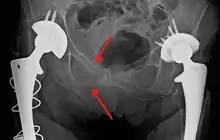

Fractures of the superior (in two places) and inferior pubic rami on the person's right, in a person who has had prior hip replacements

Pelvic fractures are most commonly described using one of two classification systems. The different forces on the pelvis result in different fractures. Sometimes they are determined based on stability or instability.[8]